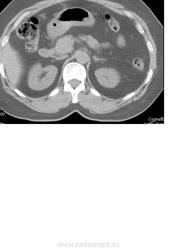

Добрый день! помогите пожалуста описать исследование. Пациентка 51 г.р., по УЗИ гипоэхогенное образование в левой доли печени 3х3,5 см с четким, неровным контуром.

Кистозное образование(?) размерами.., плотностью.. едН, расположено там то. Я думаю, что это киста.